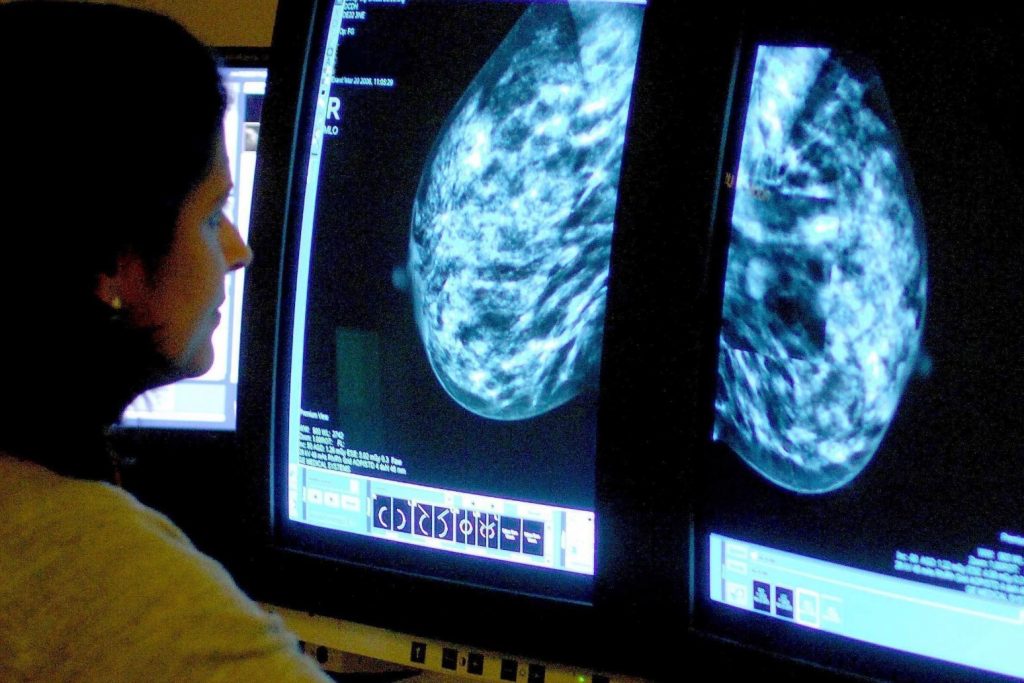

Breast cancer cases and deaths set to rise dramatically by 2050 data suggests

The number of women in the UK diagnosed with breast cancer and dying from the disease is set to rise dramatically by 2050, data suggests.